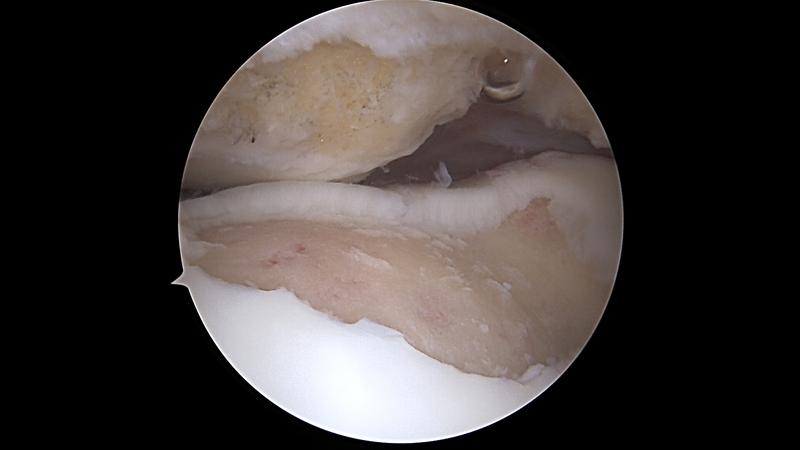

Chondromalacja rzepki to temat, który z pewnością nie jest nowością dla wielu osób, zwłaszcza tych, które doświadczyły bólu kolan. To schorzenie oznacza, że chrząstka znajdująca się pod rzepką staje się zbyt „miękka” w porównaniu do normy. Jakie zatem ćwiczenia powinny znaleźć się na czarnej liście osób cierpiących na chondromalację? Odpowiedź jest prosta: należy unikać wszelkich aktywności obciążających staw, takich jak przysiady poniżej 70 stopni czy skoki. Zamiast tego, warto wybierać bardziej przyjazne dla stawów formy aktywności, jak jazda na rowerze, która nie tylko nie szkodzi rzepce, ale wręcz wzmacnia mięśnie ud.

Chondromalacja rzepki to schorzenie, które może wywołać ból w kolanach. Zmiękczenie chrząstki rzepkowej prowadzi do różnych nieprzyjemnych dolegliwości. Aż trudno uwierzyć, że taka mała kostka potrafi tak dużo namieszać w naszym życiu! Dlatego kluczową rolę odgrywa technika wykonywania ćwiczeń. Niezależnie od tego, czy jesteś sportowym profesjonalistą, czy debiutantem, powinieneś zwrócić uwagę na to, jak traktujesz swoje kolana. Źle wykonywane przysiady czy skoki mogą przynieść więcej szkody niż korzyści. Przecież chcemy być sprężystymi zajączkami, a nie bezradnymi chrząszczami w pudle.